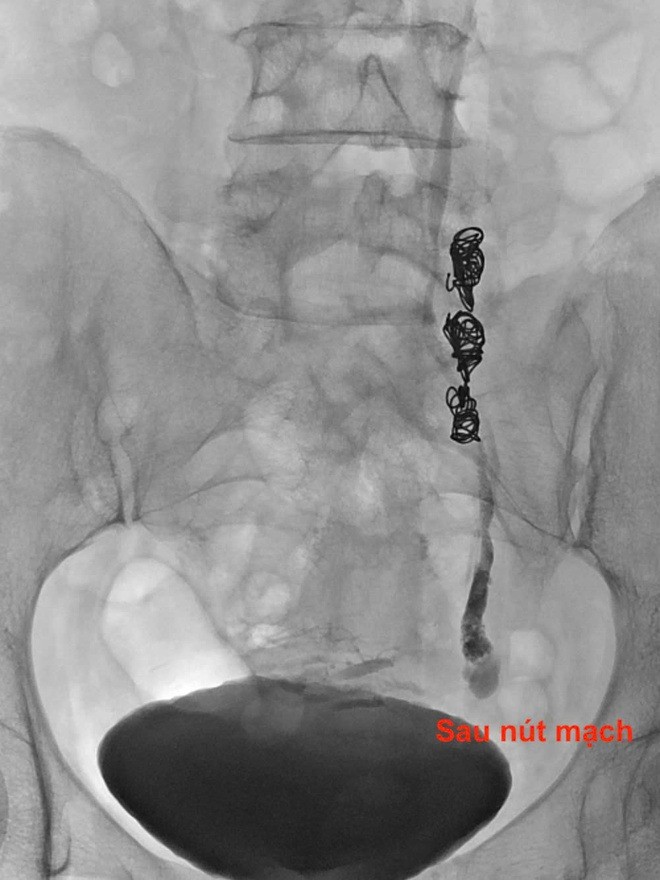

Bệnh nhân đã được can thiệp nút mạch để điều trị giãn tĩnh mạch buồng trứng.

Các bác sĩ sử dụng dụng cụ chuyên biệt để bít tắc nhánh tĩnh mạch bất thường, ngăn máu trào ngược gây đau. Ngay sau can thiệp, bệnh nhân lần đầu tiên sau nhiều năm cảm thấy cơ thể nhẹ nhõm, không còn bị "hành hạ" bởi những cơn đau bụng không lời giải thích. "Không chỉ là khỏi bệnh, mà điều quan trọng hơn, tôi đã được tin – rằng cơn đau của mình là có thật," bệnh nhân xúc động nói.